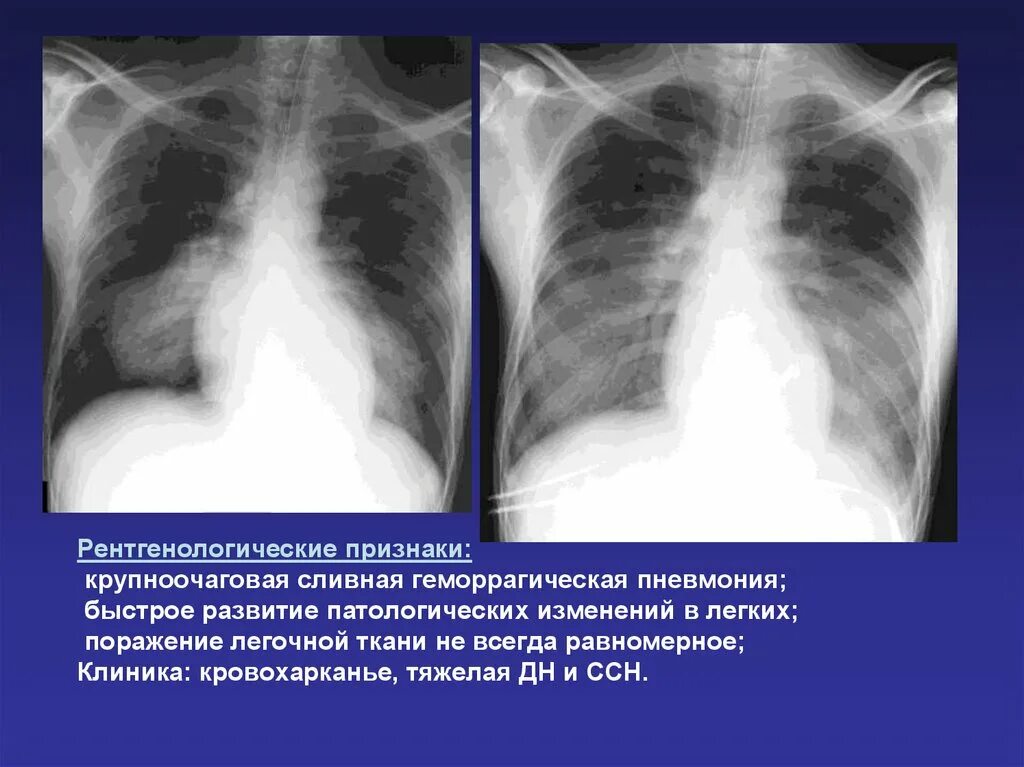

Пневмония сколько поражение легких